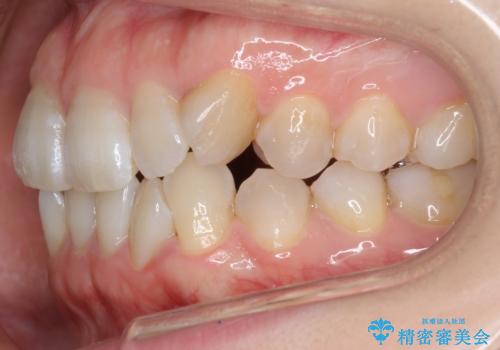

- 前歯のねじれを主訴に来院。

レントゲンを撮影したところ、右下4は神経のない歯で、外部吸収といって、根がだんだん短くなり、やがて抜けてしまう症状になっていました。また、アンキローシスを起こしている可能性があるため、動かない可能性が高い状態でした。

上顎前歯も唇側傾斜しておらず、もともと叢生が多くない状態で上下左右を抜歯した上、リンガルで治療を行なったため、多少治療期間がかかりました。